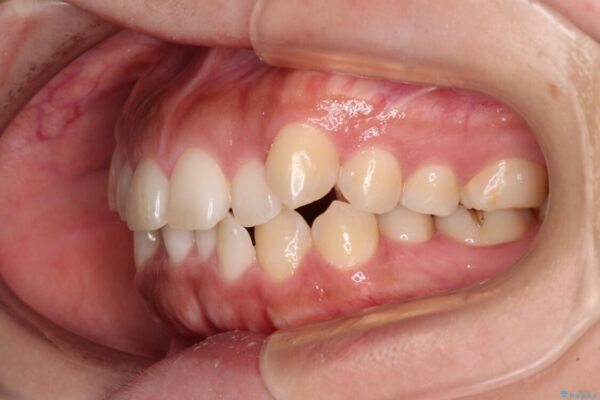

前歯の叢生と八重歯を気にして来院された患者様です。

治療前

• 【モニター】カリエール・ディスタライザーを併用した八重歯のインビザライン矯正 治療前画像